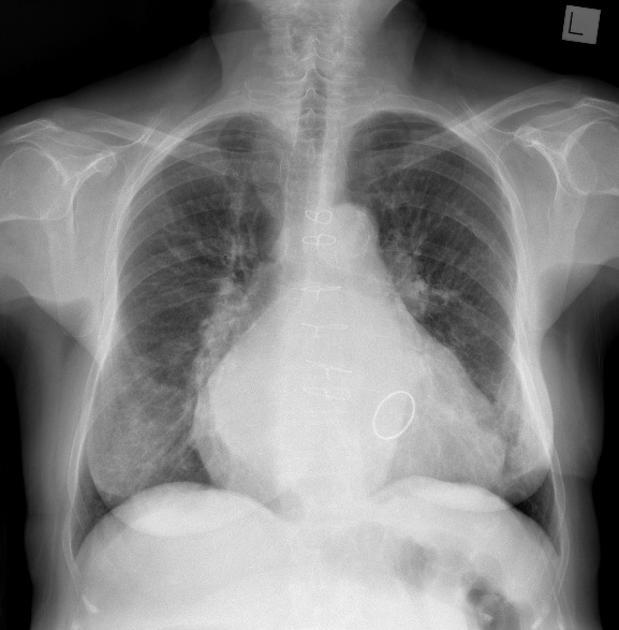

What is going on in this radiograph?

This patient had a left pneumonectomy!

The left lung is gone, and the trachea and heart have moved over to fill the void.